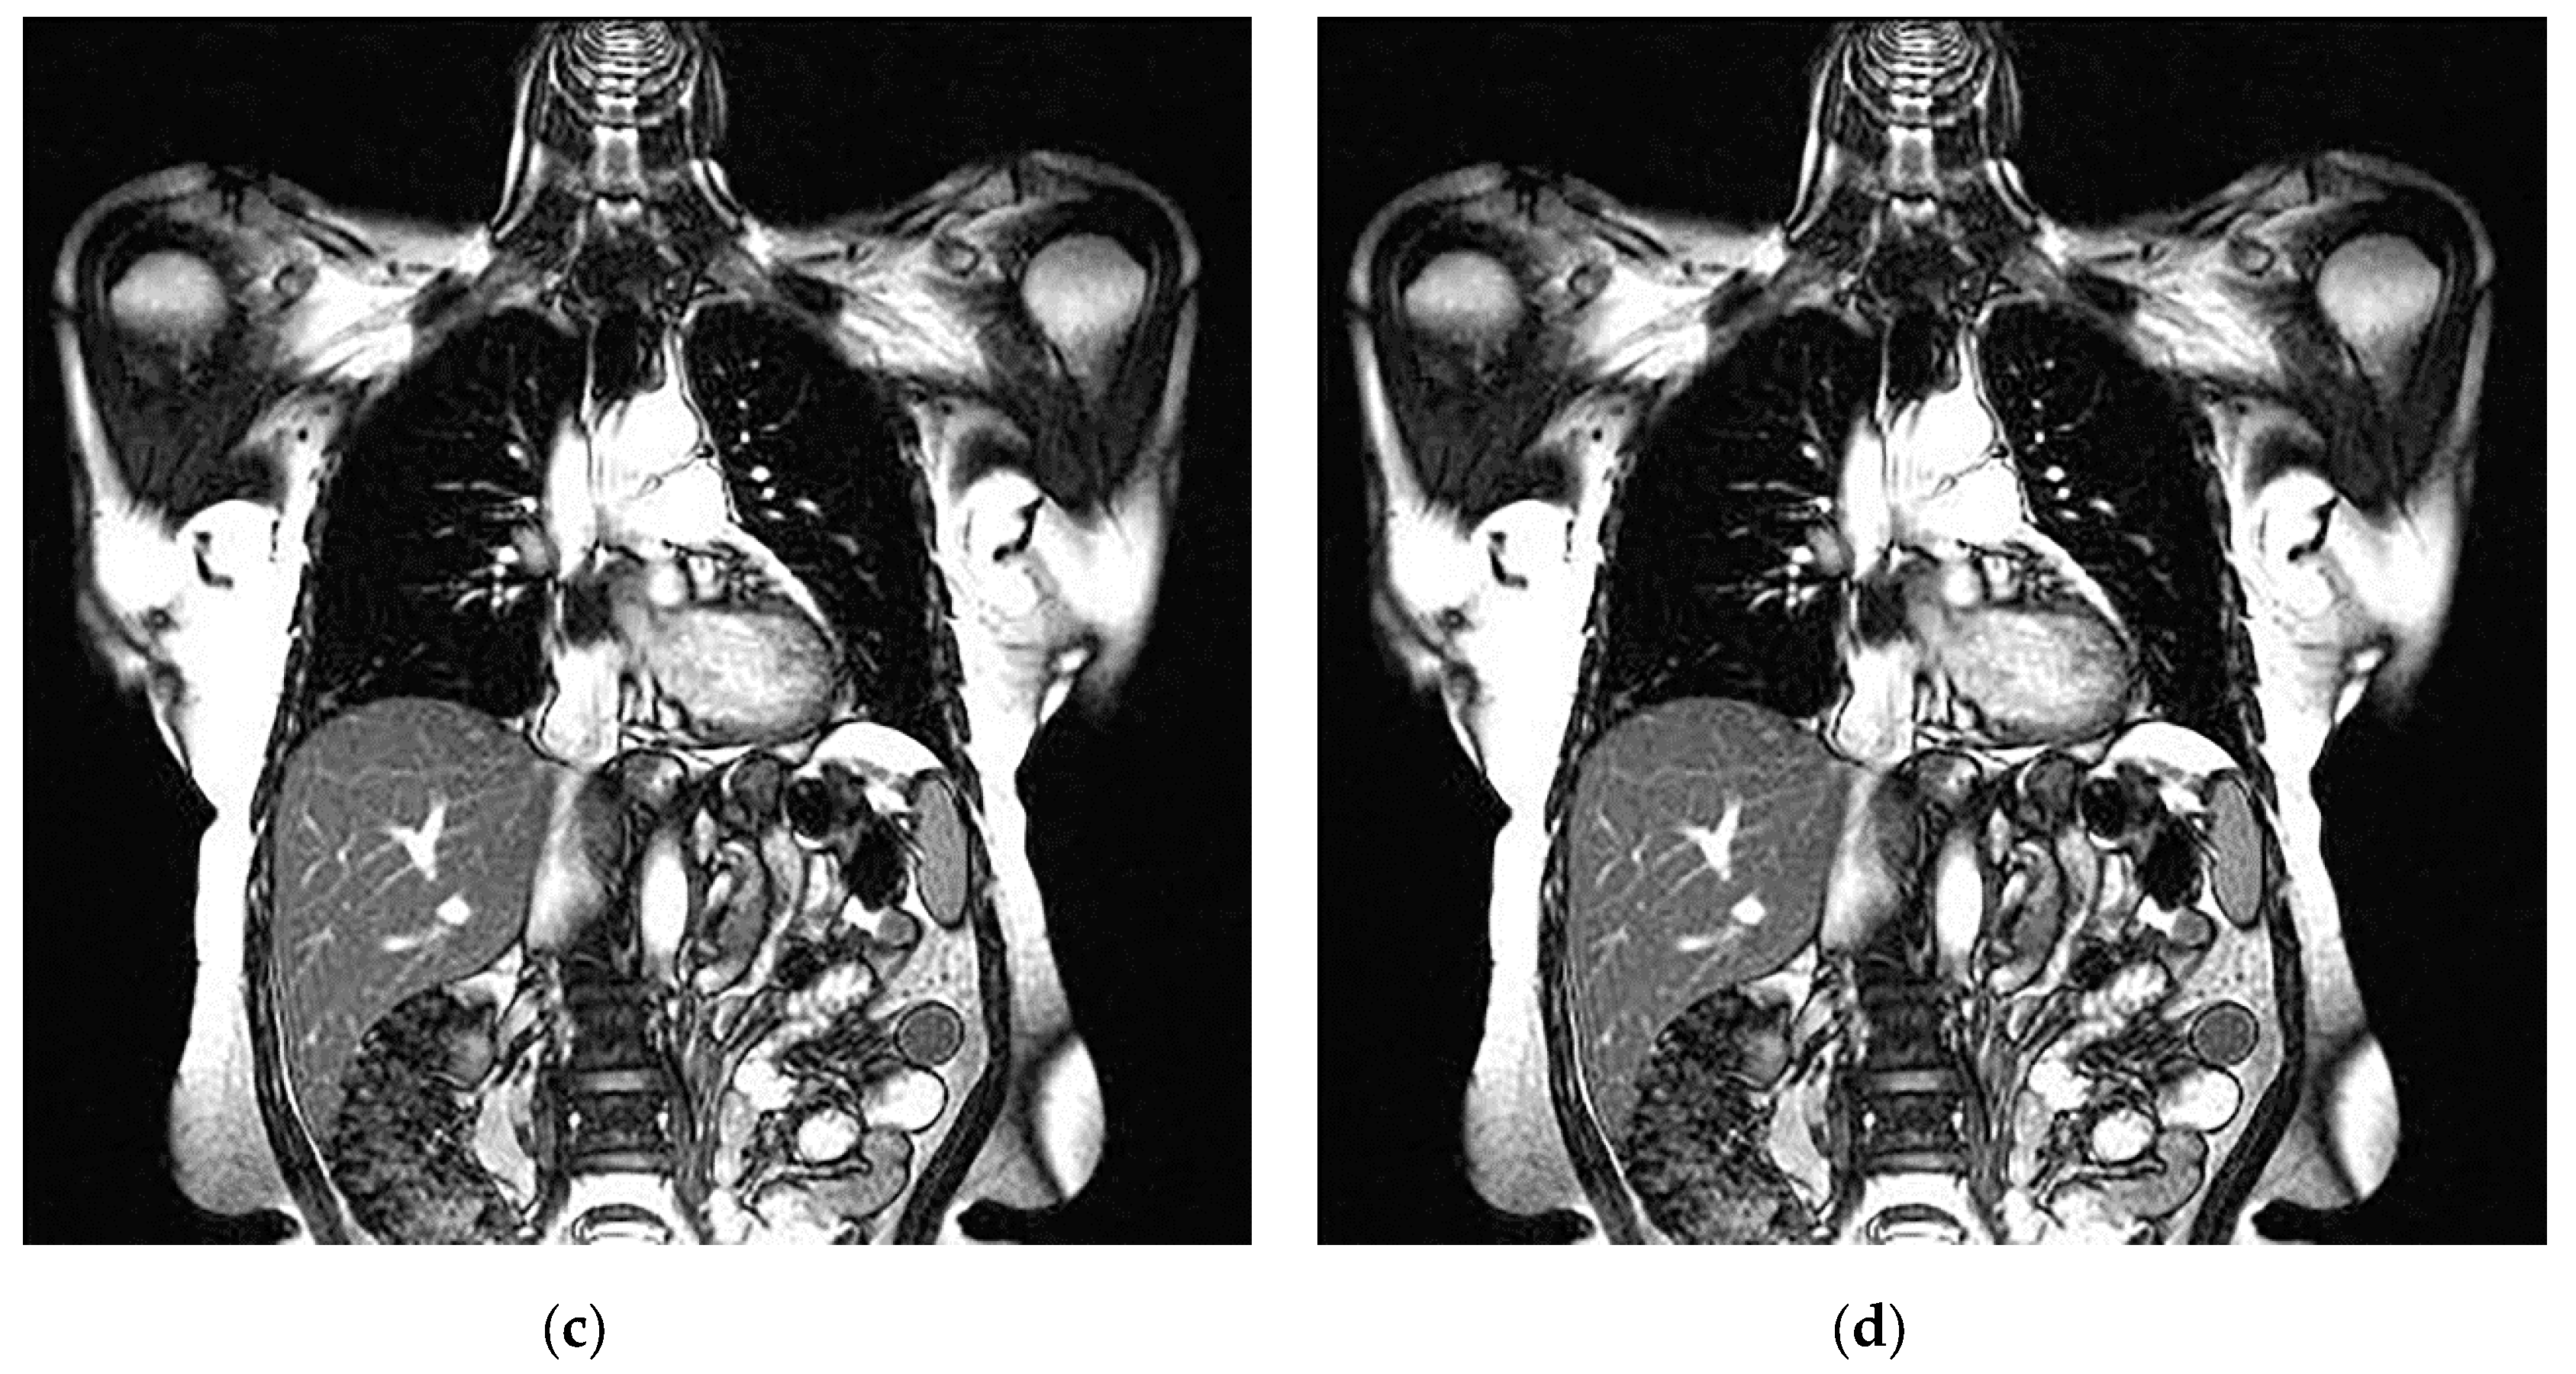

An example of 3D tomographic images “wmri”, “Trufi_COR” and “Body_1.0” DWT with wavelet is shown in Figure 5, Figure 6 and Figure 7 respectively. Frames in Figure 6 and Figure 7 are selected to illustrate the error effect on the image processing result. Figures show a gradual improvement in the quality of processing with an increase the bit-width : in Figure 5b, Figure 6b and Figure 7b visible distortion (Figure 5b is darkened in places, and Figure 6b and Figure 7b are lighted); in Figure 5c, Figure 6c and Figure 7c processed images are indistinguishable by eye from the original images; in Figure 5d, Figure 6d and Figure 7d processed images are identical to the corresponding originals. Experimental results are of higher quality compared with the calculation results. The values dB and at and respectively (Figure 5) obtained after 8-bit image “wmri” DWT with wavelet exceed the corresponding calculated values dB and at and respectively (Table 1). The values dB and at and respectively (Figure 6) obtained after 12-bit image “Trufi_COR” DWT with wavelet exceed the corresponding calculated values dB, dB at and respectively (Table 2). Similarly, for “Body_1.0”.

Figure 7.

Example of 3D tomographic 16-bit image “Body_1.0” (1-st frame) DWT by wavelet: (a) original image; processed image: (b) , dB; (c) , dB and (d) , .